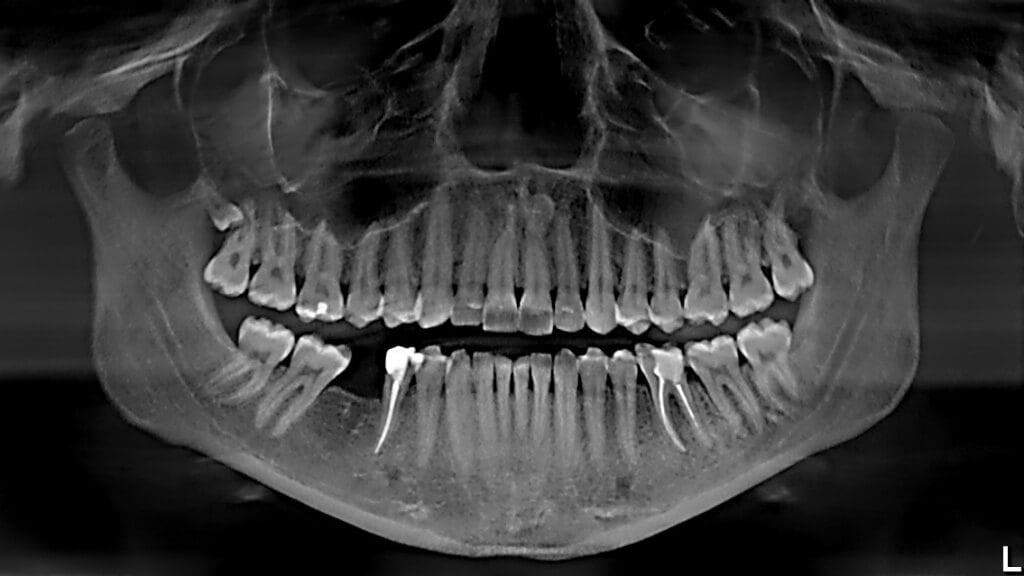

Знаете ли вы, что здоровье человеческого организма зависит от стоматологического здоровья? Проблемы с зубами и дёснами могут привести к неожиданным последствиям — не только усугублению имеющихся проблем со здоровьем, но и развитию серьезных болезней по всему телу человека. Да, это не шутки. И неприятный запах изо рта в этом случае — это цветочки. Незнающий человек никогда не заподозрит связь между больным ртом и проблемами с сердцем, дыхательными путями, пищеварительной системой, суставами. Будет удивляться и лечить симптомы, не догадываясь о первопричине — больных зубах и дёснах, игнорируя их (ведь жить не мешает, значит подождёт), а они будут продолжать разрушать здоровье. Возникают вопросы — как и почему? Как так получается, что больная полость рта, больные зубы негативно влияют на наше здоровье, на весь человеческий организм? Одна из причин заключается в том, что воспаление зубов и дёсен, инфекции, кариозные полости, пародонтит и образование кист, одним словом, — проблемы полости р

Знаете ли вы, что здоровье человеческого организма зависит от стоматологического здоровья? Проблемы с зубами и дёснами могут привести к неожиданным последствиям — не только усугублению имеющихся проблем со здоровьем, но и развитию серьезных болезней по всему телу человека. Да, это не шутки. И неприятный запах изо рта в этом случае — это цветочки. Незнающий человек никогда не заподозрит связь между больным ртом и проблемами с сердцем, дыхательными путями, пищеварительной системой, суставами. Будет удивляться и лечить симптомы, не догадываясь о первопричине — больных зубах и дёснах, игнорируя их (ведь жить не мешает, значит подождёт), а они будут продолжать разрушать здоровье.